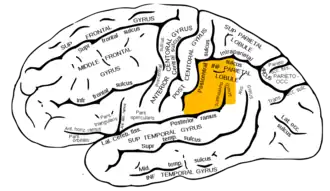

Lateral surface of left cerebral hemisphere, viewed from the side (supramarginal gyrus shown in orange) | |